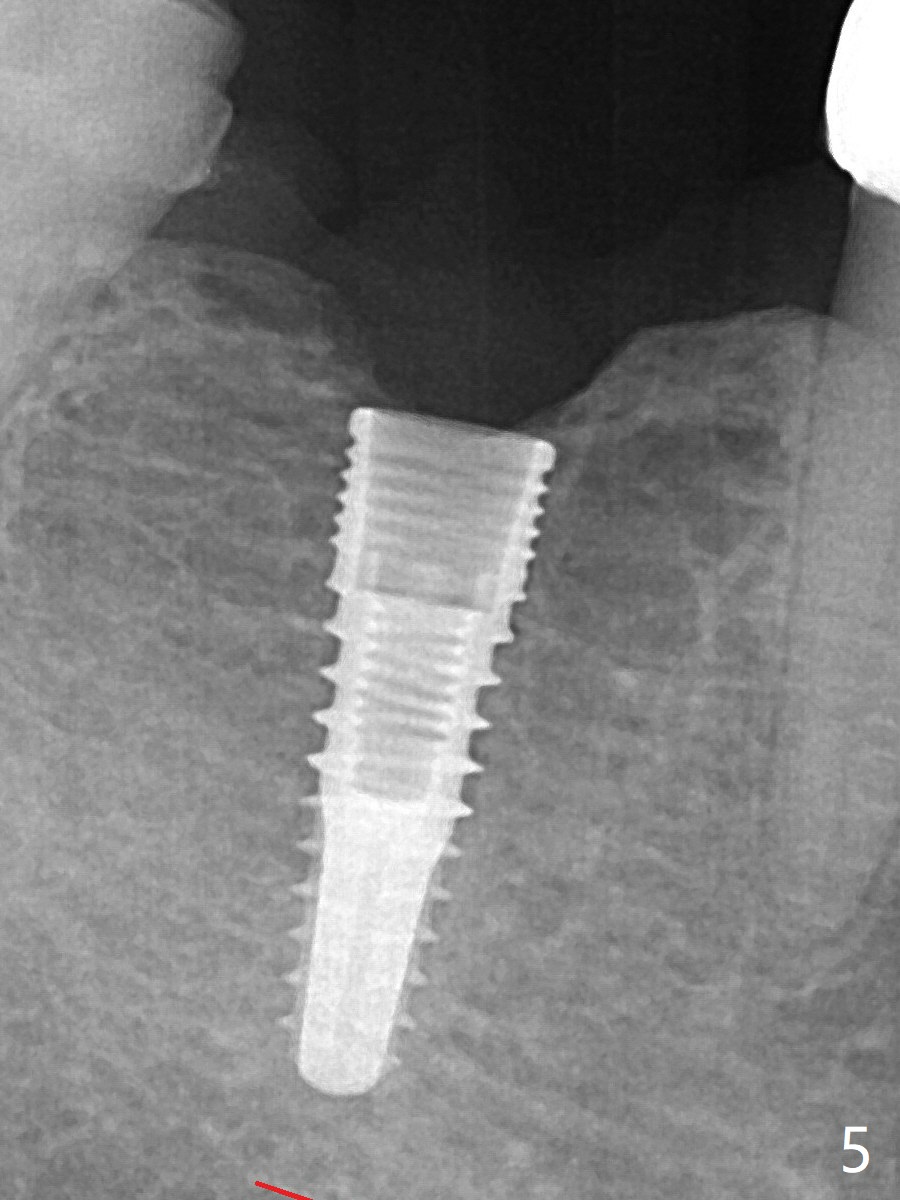

When a 3.8x12 mm SM implant is placed with 40 Ncm, there is 1-2 mm cortical bone buccolingually (primary stability, Fig.4,5). The thick cortices do not seem to be easy to be bent, i.e., expanded.